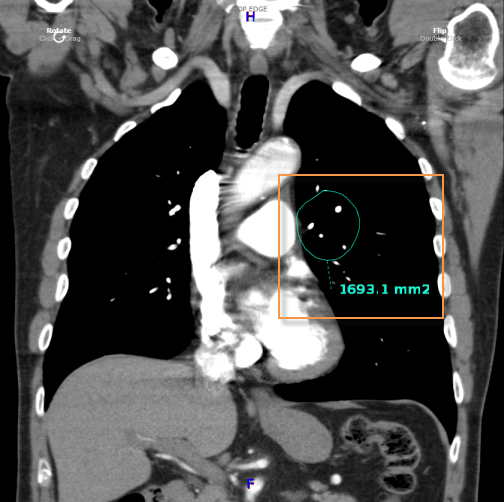

A vizsgált terület (ROI) mérésének menete:

Válassza a vizsgált terület (ROI) ![]() ikont

ikont

Kattintson a vizsgált területre

Húzza az egeret a terület meghatározásához

Engedje el az egérgombot

A középső fogóponttal  mozgathatja az ROI-t a képen, a többivel pedig nyújthatja vagy keskenyítheti.

mozgathatja az ROI-t a képen, a többivel pedig nyújthatja vagy keskenyítheti.